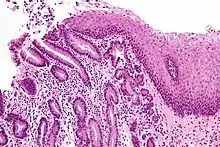

| Micrograph of a gastro-esophageal junction with pancreatic acinar metaplasia. The esophageal mucosa (stratified squamous epithelium) is seen on the right. The gastric mucosa (simple columnar epithelium) is seen on the left. The metaplastic epithelium is at the junction (center of image) and has an intensely eosinophilic (bright pink) cytoplasm. H&E stain. |